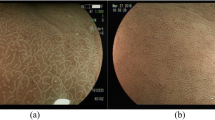

This work aimed to improve the early clinical diagnosis rate of atrophic gastritis (AG) and reduce the risk of disease deterioration or cancerization. Three hundred and eight patients with gastric disease were taken as the research object, who were divided into two groups: AG (n = 159) and non-AG (n = 149), according to the diagnosis results. The gastric antrum images of patients were collected, and the DenseNet model for gastric antrum image lesion screening was improved. Then, the differences in serum pepsinogen (PG I and PG II) of patients were detected, and the efficiency of different methods to screen AG was compared. The results revealed that the levels of PG I and PG II in AG patients were substantially reduced, and the sensitivity (70.44%), specificity (66.44%), and accuracy (68.51%) of AG diagnosis by indicator PG I were higher than that of PG II and joint diagnosis. The diagnosis accuracy rate of AG based on the improved DenseNet model was 98.63%. The accuracy of model recognition combined with serological indicators for disease diagnosis was as high as 99.25%, with a sensitivity of 96.17% and a specificity of 94.33%. In summary, the combination of deep learning-based image recognition methods and serological specific indicators could improve the clinical diagnosis rate of AG, which could provide a reference for the subsequent clinical adoption of artificial intelligence recognition technology.